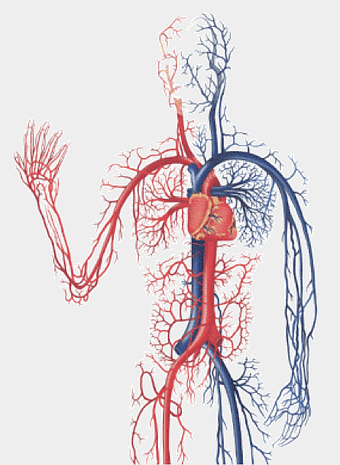

human circulatory system diagram, blood vessel network illustration, human anatomy chart, cardiovascular system overview, human body medical illustration, physiological system depiction, organ function visualization -

human heart diagram, cardiovascular system anatomy, blood vessel chart, free body diagram, circulatory system illustration, medical organ visualization, human anatomy study -

blue human anatomy illustration, human circulatory system diagram, digital human skeleton image, electric blue medical figure, human nervous system visualization, human body organ map, human health care graphic -

heart anatomy illustration, cardiovascular system diagram, circulatory system medical, vascular system sonography, human body blood flow, arterial network visualization, heart function analysis -